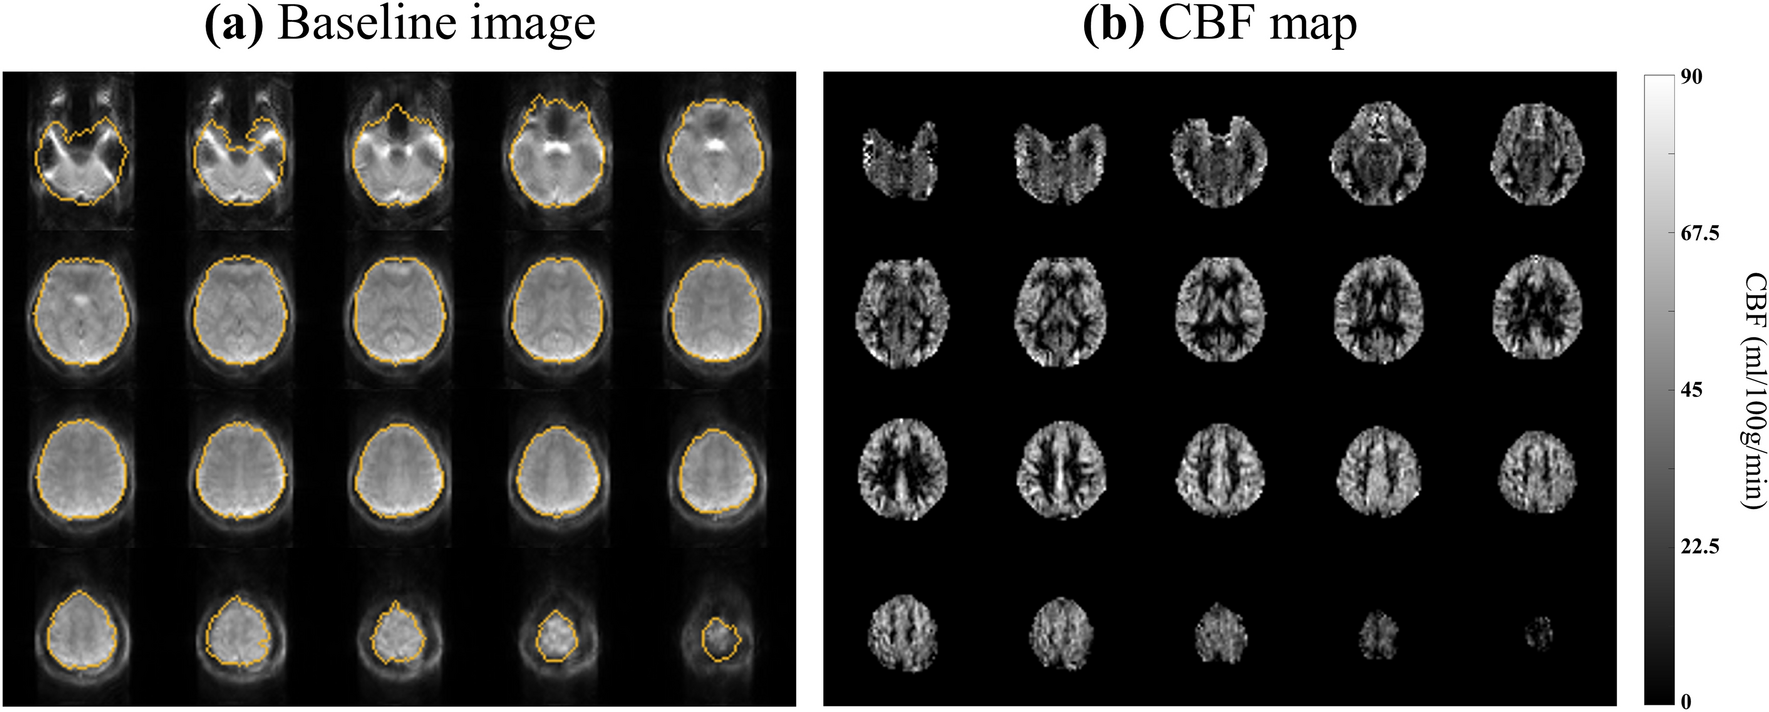

Figure 6

From: Distortion correction using topup algorithm by single k-space (TASK) for echo planar imaging

Whole-brain (a) baseline image and (b) perfusion map from a representative subject (Subject #1). (a) The orange lines represent the ground truth brain boundary from GRE images.